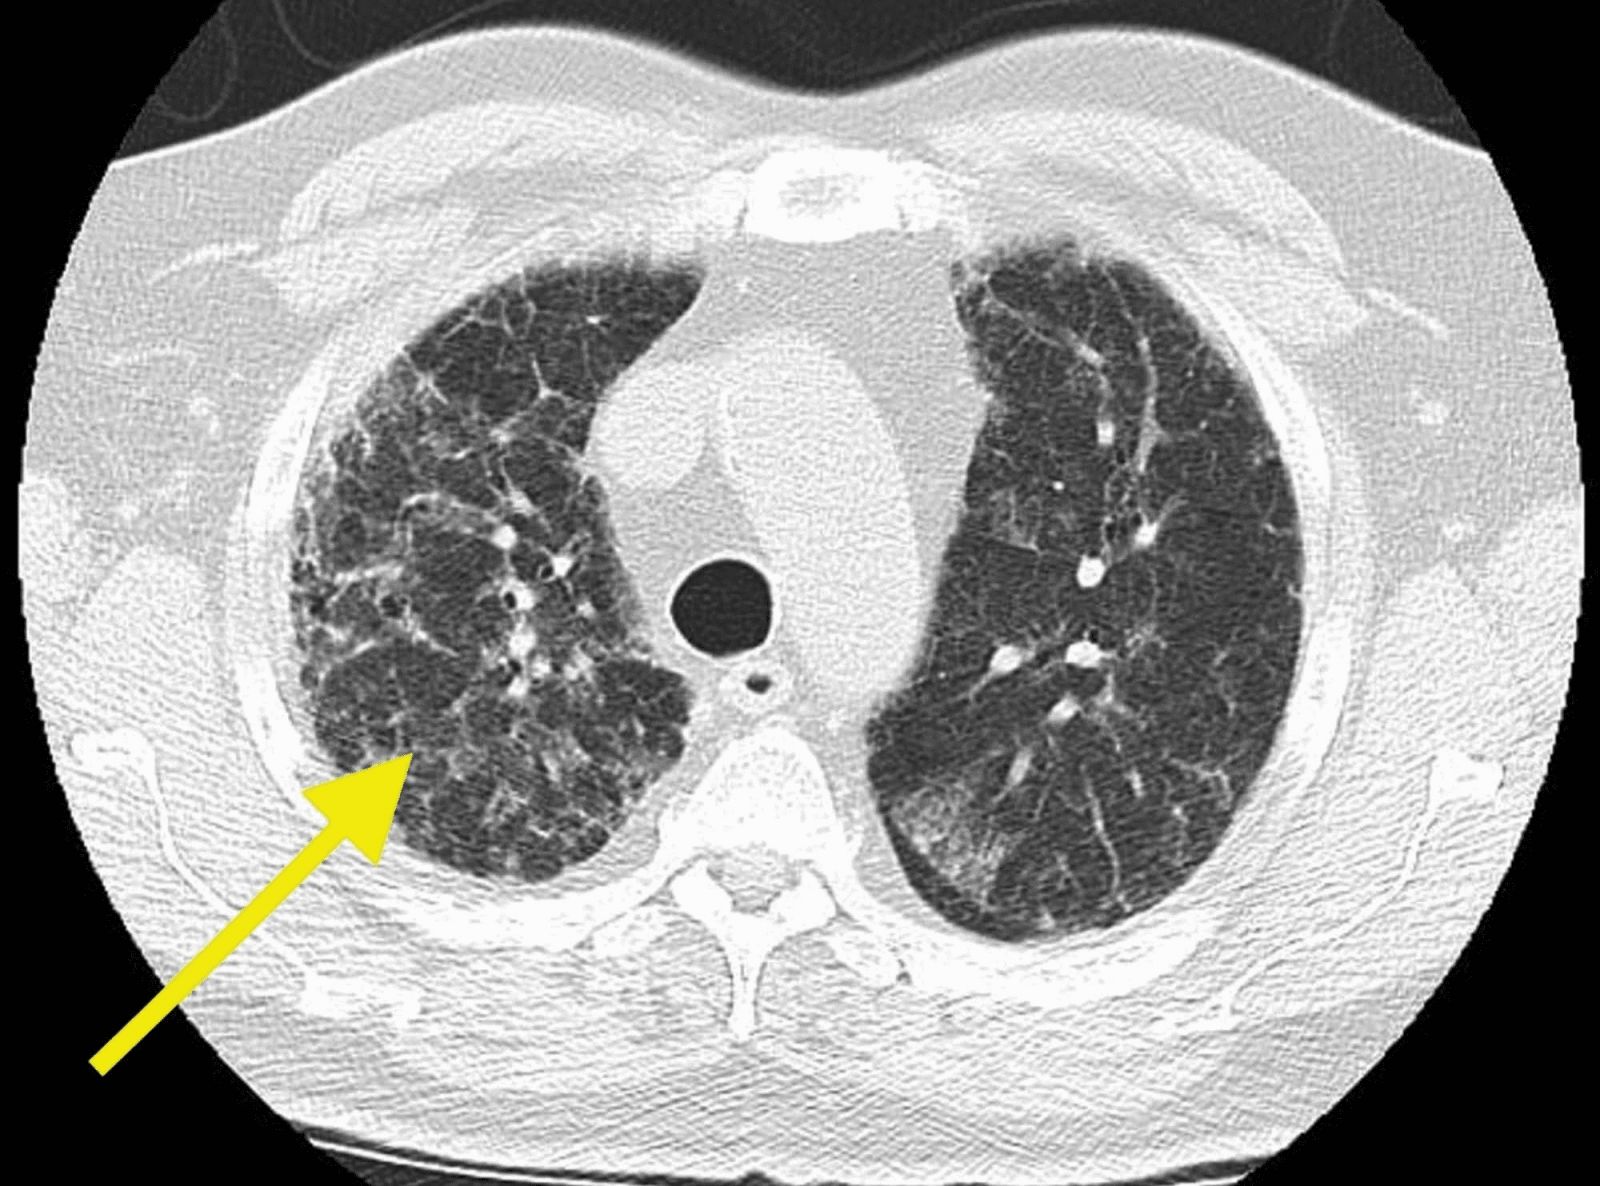

КТ ретроперитонеального фиброза: Изображения и диагностика